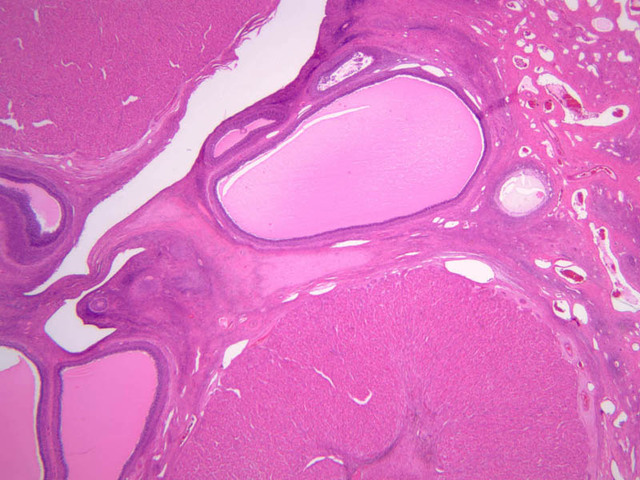

The resting or inactive mammary gland consists of predominantly dense connective tissue with small clusters of ducts and a few glandular elements (slide A-93 [2.5x-labeled, 10x, 20x, 40x] [1x, 2.5x, 10x, 20x]). It is difficult to differentiate between small ducts and alveoli as each is lined by simple low cuboidal cells. Lobes and lobules are not well defined. During puberty, predominantly under the influence of the ovarian hormone estrogen, the glandular or epithelial ducts proliferate and begin to differentiate into clusters of ductal and alveolar units termed terminal ductal lobule units (TDLUs). The non-pregnant gland will form multiple TDLUs that will not fully differentiate until pregnancy-induced growth. TDLUs are classified into Type I, Type II and Type III based on density of the ductules within each lobular unit. Type I and Type II lobules are typical of inactive glands that have not undergone a pregnancy cycle. Type III lobules are seen only in active glands or in inactive glands that have been through a pregnancy. Intralobular connective tissue is loose connective tissue that surrounds the alveoli and ducts within a lobule. The interlobular connective tissue is dense and contains considerable adipose tissue.